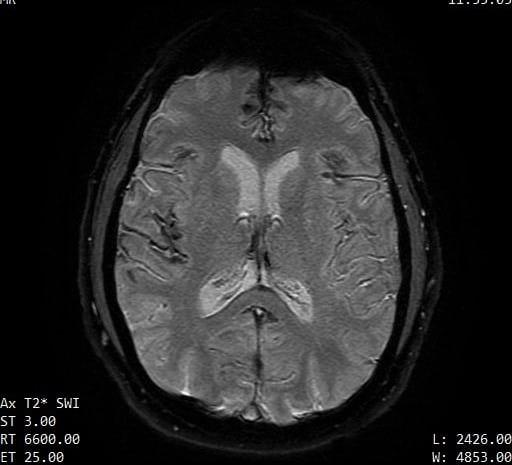

The contours of the cerebrum, cerebellum, and brainstem are outlined with a T2 hypointense signal with blooming on susceptibility weighted sequences, which is compatible with the clinical history of superficial siderosis. A majority of the T2 hypointense signal is present in the superior folia of the cerebellum but also seen coating the surfaces of the brainstem, the cortical surfaces along the Sylvian fissures, and the cortical surfaces of the paramedian sulci of the frontal and occipital lobes. Few subcortical and periventricular T2/FLAIR hyperintensities are present in both cerebral hemispheres.²

If you look at each image, you can see the dark areas where his hemosiderin deposits are. The radiologist will use the same machine and settings, so we should visually compare the new images with these for some positive change.³